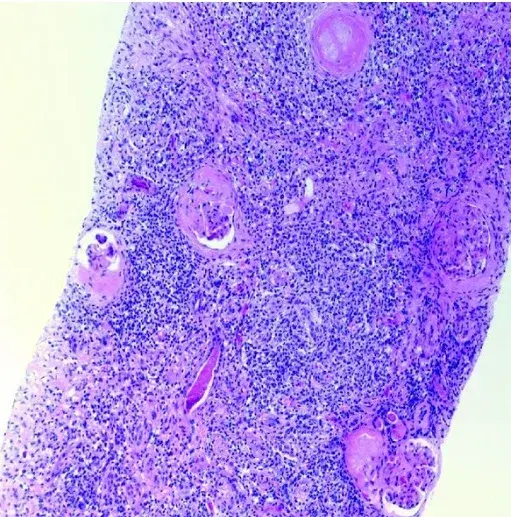

Caso muito ilustrativo publicado no Kidney 360 (link) Paciente do sexo feminino com 43 anos e com antecedente de nefrite lúpica (NL) proliferativa há 13 anos. A paciente apresentava histórico de acometimento grave da doença, com múltiplos tratamentos com infusões de metilprednisona e ciclofosfamida devido ao acometimento do sistema nervoso central (SNC) e da NL.